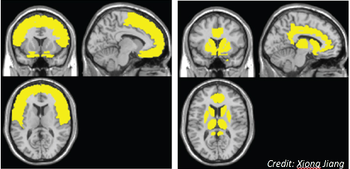

A neural model suggests the frontal lobe is affected early on in HIV disease and the caudate/striatum area is affected when neurocognitive disorder symptoms develop.